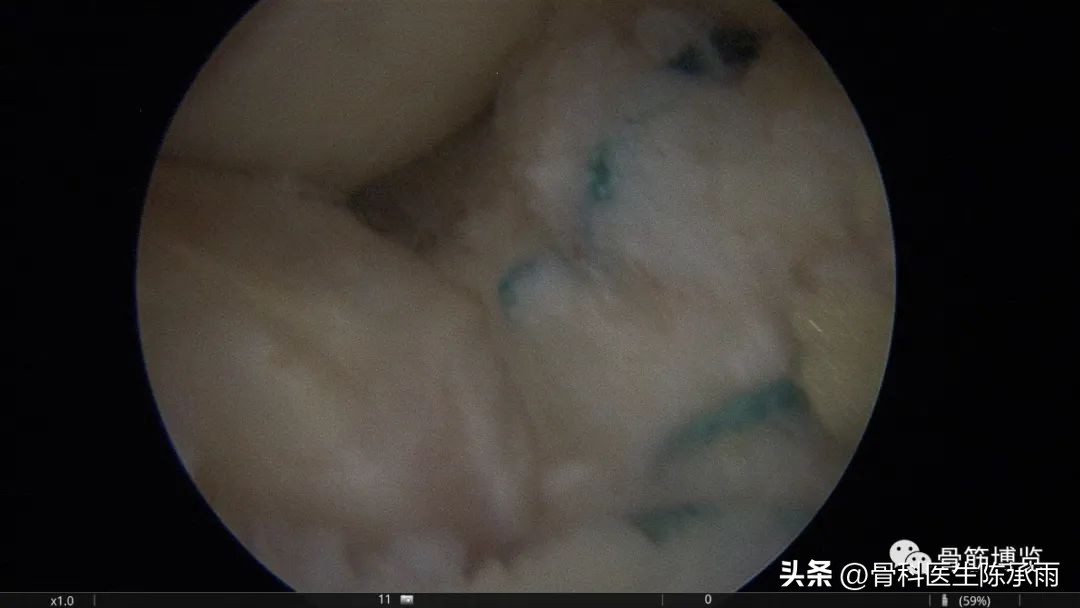

本例为内侧半月板前角巨大囊肿,关节镜下行半月板囊肿引流减压+囊肿前壁及囊壁滑膜切除+半月板缝合术。术中切除全部囊壁内滑膜及前壁及大部分后壁,保留部分后壁组织,以保证半月板前角缝合可靠及稳定。

术中情况

半月板囊肿分型决定了治疗方法的选择,对于前两种半月板囊肿因伴有半月板的损伤治疗方法相对复杂,半月板囊肿合并的半月板损伤多为水平撕裂或复杂撕裂,而且病史较长,因此需严格掌握缝合手术的指证。手术操作要点:采用常规的髌下内侧和髌下外侧入路,探查关节内囊肿和半月板撕裂的大致范围;使用刨刀细致地将囊肿切除,尽量彻底切除囊壁,充分敞开囊腔,避免囊肿复发,囊肿内可有分房或分隔现象,注意避免遗漏。注意在手术时尽量保留冠状韧带,避免冠状韧带的广泛缺损;进一步仔细探查损伤的半月板组织,明确撕裂的范围在红﹣红区或红﹣白区,对于超出上述范围的损伤或半月板的复杂撕裂及水平撕裂,放弃缝合手术,如条件许可时可在切除部分半月板(如切除水平撕裂的两片中不稳定的一片)的基础上进行缝合手术。然后以刨刀或磨钻小心修整损伤的半月板组织,使对合面整齐并显露新鲜组织;髌下外侧人路置人工作套管,附加经髌韧带的正中入路,严格解剖复位。经正中人路置人探针,固定半月板撕裂部位,使用肩袖缝合器经髌下外侧入路工作套管,缝合器尖端首先由半月板前缘和冠状韧带的交界处穿人半月板下表面后,越过半月板裂隙,在对侧由下到上穿出半月板上表面,经工作套管将线导出,体外打 Duncan 结,推线器将线结推人至半月板前缘处拉紧,再打两个套结,剪断缝线。两缝线之间间距8 mm 。滑膜囊肿的手术操作相对简单:镜下切除囊肿后,将半月板与冠状韧带之间的缺损区缝合。